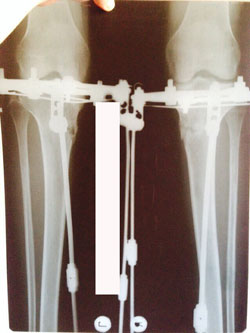

Дата операции 23.01.2015г.

Дата снятия аппаратов 28.04.2015г.

Срок лечения 95 дней.

Рентген контроль в 1,5 месяца с момента снятия аппаратов.

Всё в норме! Разрешено все нагрузки без ограничения, каблуки любых размеров! Фото на каблуках за Вами!